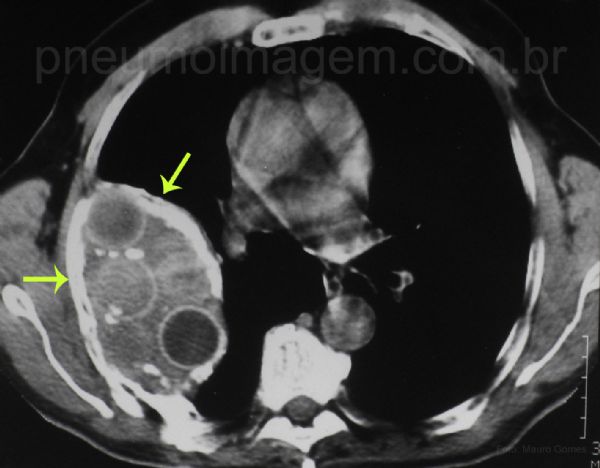

No corte tomográfico abaixo se oberva uma opacidade heterogênea com grande espessamento da pleura ao seu redor (setas amarelas) e imagens circulares no seu interior com elevada densidade periférica e interior com densidades variáveis, que correspondem às bolas de Lucite.

Cada uma dessas bolas costumava medir aproximadamente 2,5 cm de diâmetro (dois terços do tamanho de uma bola de pingue-pongue.

In this current CT slice there is a heterogeneous opacity with great thickening of the pleura around (yellow arrows) and circular images inside, with varying densities, which correspond to the Lucite balls. Each of these balls measuring approximately 2.5 cm (1 in.) in diameter (two-thirds the size of a ping pong ball). Key: plumbago.